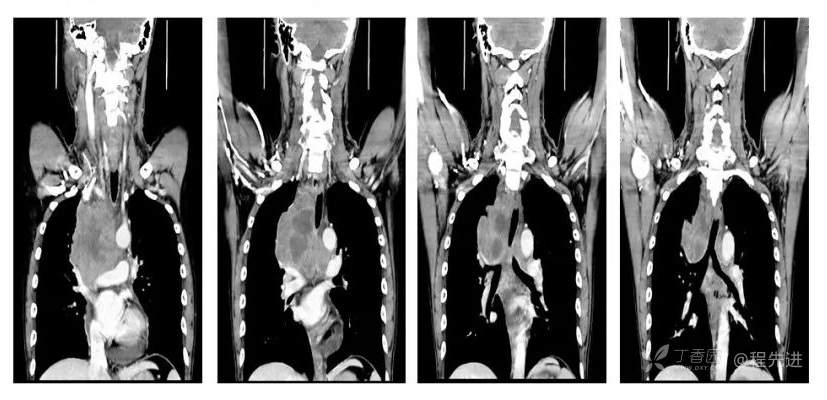

CT

平扫CT值约38HU,动脉期CT值约46HU,静脉期CT值约58HU